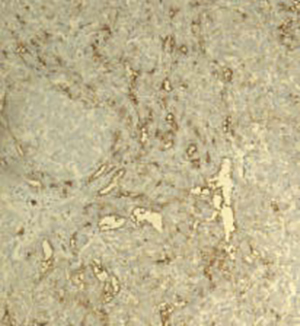

Figure 4: Immunohistochemical stains, sex cord markers

UTROSCT expresses a variable immunoprofile with possible positive or negative staining for any of the commonly used sex cord markers, including inhibin, calretinin, SF1, WT1, and FOXL2. Co-expression of epithelial and muscle markers is common. UTROSCT is also typically positive for CD10 and less commonly positive for ER and PR. The differential diagnosis includes endometrial stromal tumor with sex cord-like differentiation, endometrial carcinoma with sex cord-like differentiation, adenosarcoma with extensive sex cord-like differentiation, and mesonephric adenocarcinoma. These entities can be distinguished based on a combination of histopathologic features, immunophenotyping, and molecular analysis.